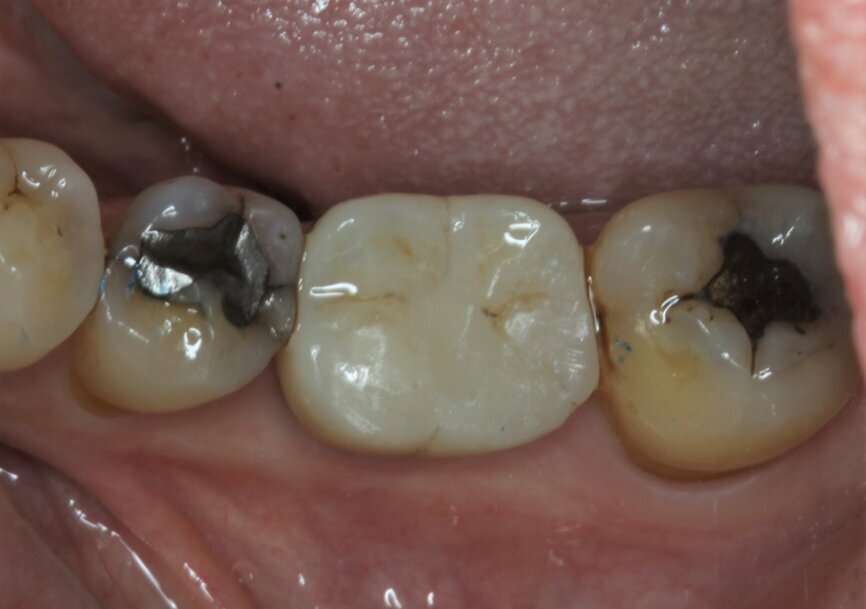

Fig. 27: Straumann TLX one-year follow-up clinical outcome.

Fig. 28: Straumann TLX one-year follow-up clinical outcome.

From a clinical perspective, the immediate placement and function were very well indicated as they could be verified through the gingival margins and health, and bone levels throughout the healing phase, and final and one-year follow-up images (Figs. 24–29).